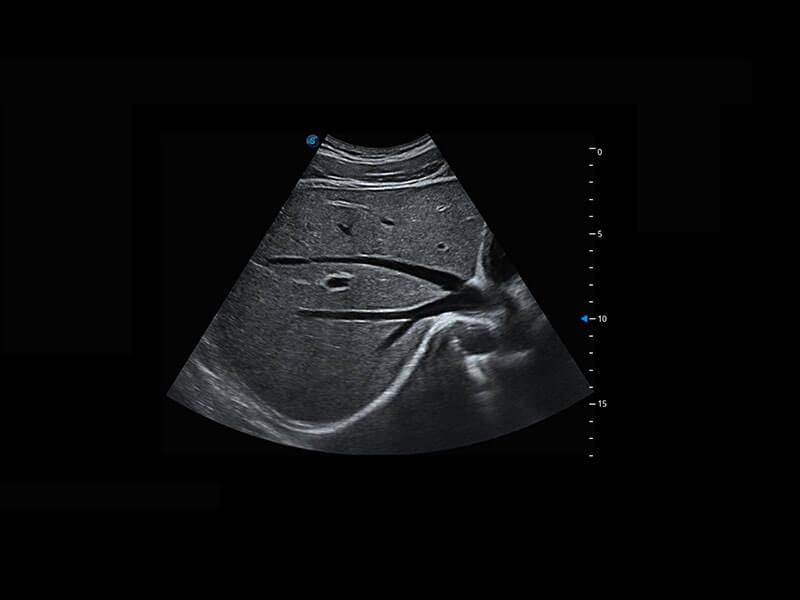

P60优异的图像质量搭载专科探头,在妇科基础疾病的诊断、卵泡生长的监测、输卵管通畅情况的判别等方面为您提供生殖应用方案。

腔内妇科-宫腔分离

腔内妇科-卵巢